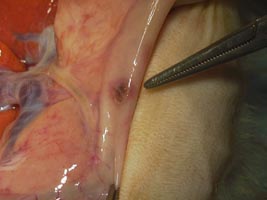

副腎腫瘍と悪性リンパ腫で死亡したフェレットの解剖写真です。貴重な画像です。

| H13.7月 | 副腎摘出手術。血管と癒着しているので左側の一部のみ摘出。組織検査はせず。 |

| H14.3月 | 死亡 解剖の結果、肺・肝臓・膵臓・副腎に転移。悪性リンパ腫との診断。 |

核小体明瞭な不整形の核と乏しい胞体を有するリンパ球類似の異型細胞が既存の組織を置換するようにびまん性に増殖している。